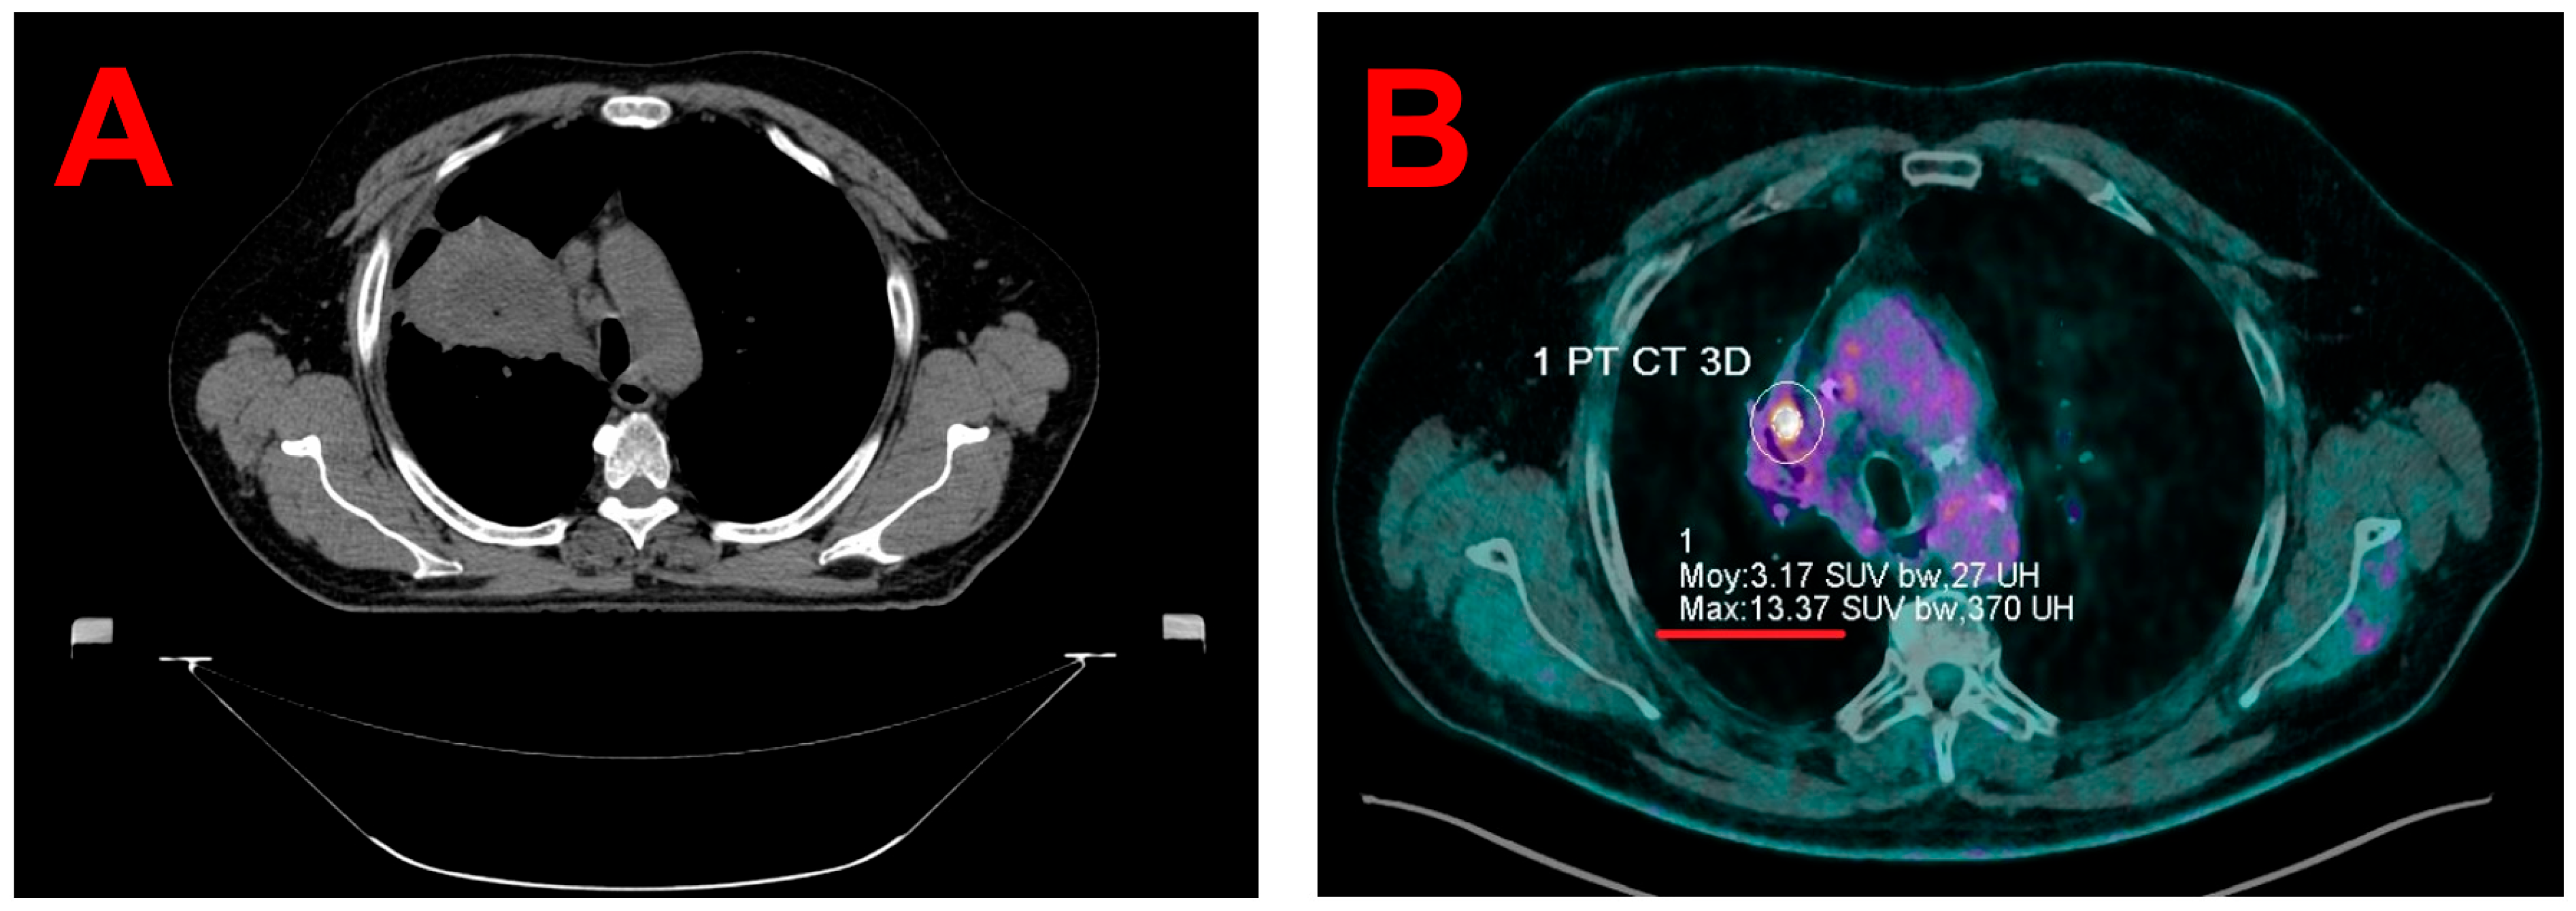

2.2. Planning Image Acquisitions

2.3. Target Volume Segmentation